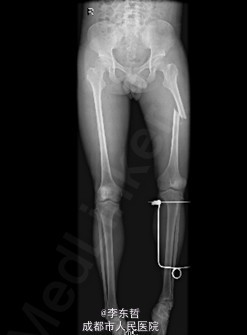

患者男,19岁,因“车祸伤致左下肢活动障碍5小时”入院。5小时前,患者骑电瓶车不慎与另一电动摩托车相撞倒地,当即感左大腿疼痛,畸形,活动受限,右小腿皮肤挫伤、出血,无头晕头痛,无大小便失禁。就诊于当地医院,检查提示:左股骨中段横行骨折。急诊行左大腿夹板外固定,右小腿清创缝合术,术后未进一步治疗,患者为进一步诊治来我院,急诊以左股骨中段骨折收入我科。 自患病以来,患者一般情况尚可,精神睡眠可,小便正常,大便未解。

查体:左大腿夹板固定,肿胀明显,短缩、畸形,右小腿内前方可见一长约5cm创口,已缝合,内植引流条一根,无明显肿胀。左大腿中段环周压痛,可扪及骨折断端,右小腿无明显压痛,双下肢感觉正常。左膝及髋关节明显活动受限,左足背及右下肢活动正常。 辅查:外院X片示:左侧股骨中上段可见骨质断裂征象,断端分离、错位、重叠,周围软组织肿胀;双侧胫腓骨、左膝关节各骨及左踝关节未见确切骨质断裂征象。

初步诊断:1、左股骨中段横行骨折,2、右小腿皮肤软组织裂伤清创缝合术后。 诊疗计划:1、向患者及家属交待病情及注意事项。2、向上级医生汇报患者病情。3、完善术前相关检查。4、给予皮肤牵引、抬高患肢等对症处理。5、拟进一步手术治疗。6、密切观察病情变化,根据病情及时处理